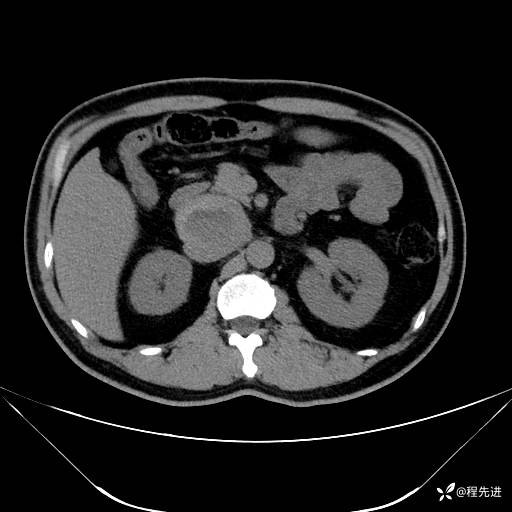

【腹盆】特别精彩病例|发现腹膜后肿物1月余

主诉:发现腹膜后肿物1月余

现病史:患者1月余前查体,行超声检查提示:后腹膜囊实性肿块;慢性胆囊炎伴胆囊内结石;无腹痛腹胀,不伴腹泻发热等;偶感腰背部酸痛。

CT平扫+增强: